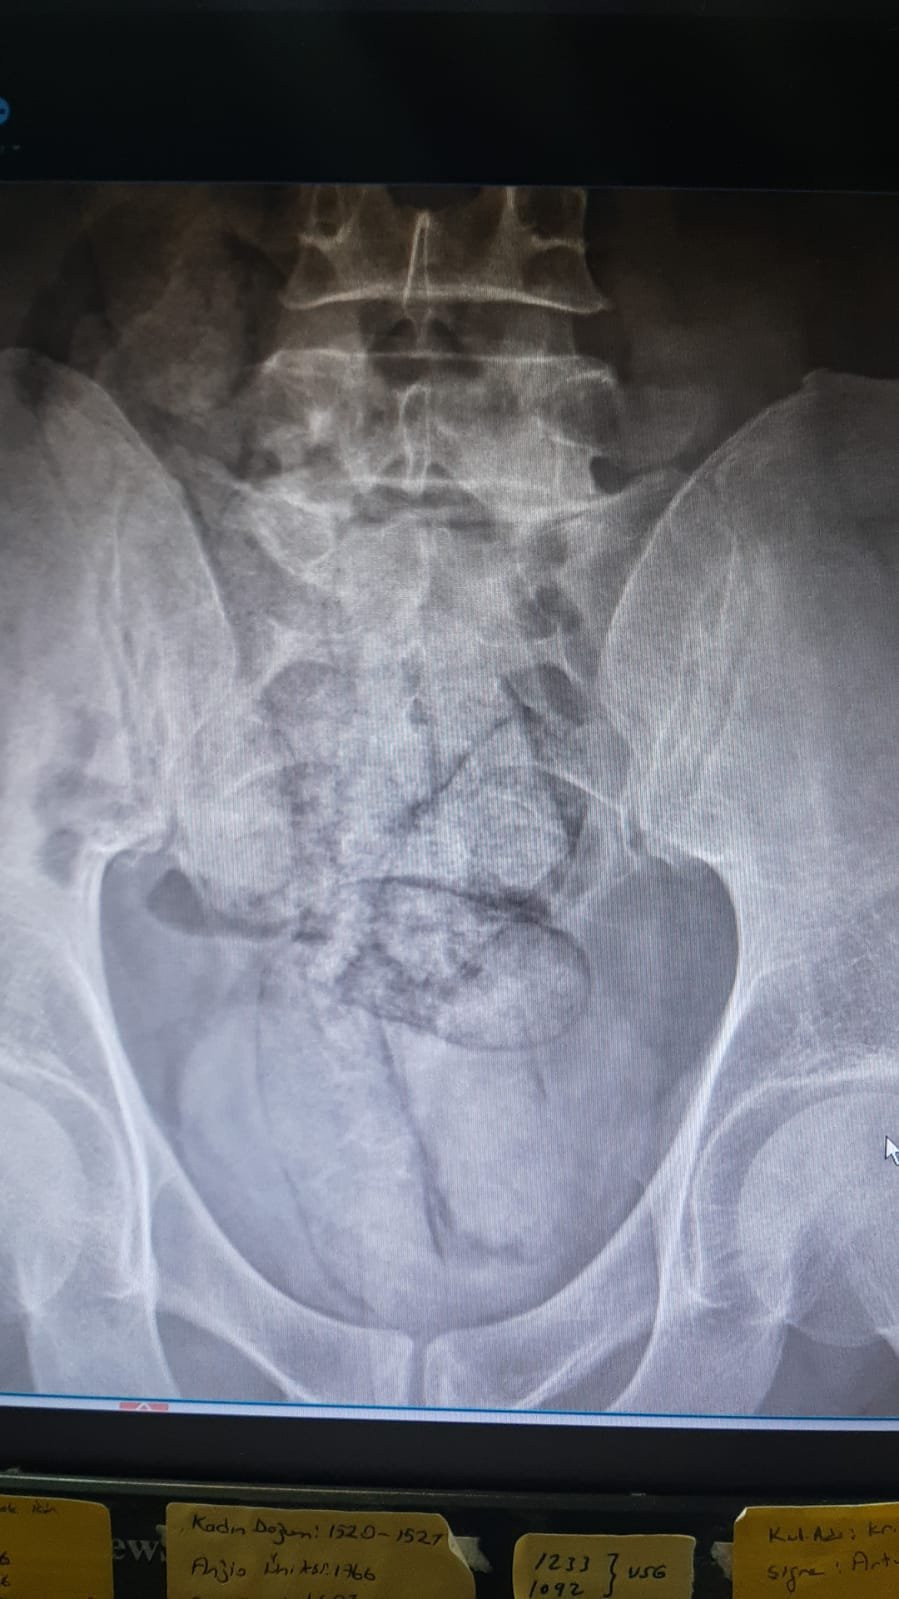

İl jandarma ekipleri, takip ettikleri İran uyruklu şüpheliyi dün saat 02.00 sıralarında Çayağzı Mahallesi'nde durdurdu. Üzerinde yapılan aramada herhangi bir olumsuzluğa rastlanmayan F.R., detaylı kontrol için hastaneye götürüldü. Artvin Devlet Hastanesi'nde tomografisi çekilen şüphelinin bağırsaklarında 10 paket halinde uyuşturucu madde taşıdığı belirlendi. Şüphelinin hayati tehlike oluşturabilecek şekilde sakladığı paketler, cerrahi müdahaleyle çıkarıldı. İncelemede paketlerin içinde toplam 350 gram metamfetamin olduğu tespit edildi.